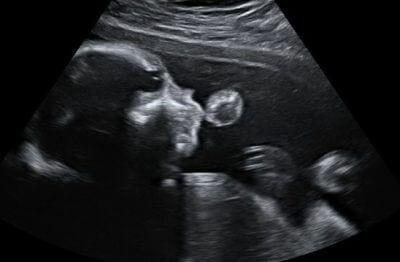

Благодаря тому, что препарат полисорб не расщепляется и не всасывается в слизистую кишечника, лекарство не попадает в системный кровоток, и, следовательно, абсолютно безопасно для ребенка.